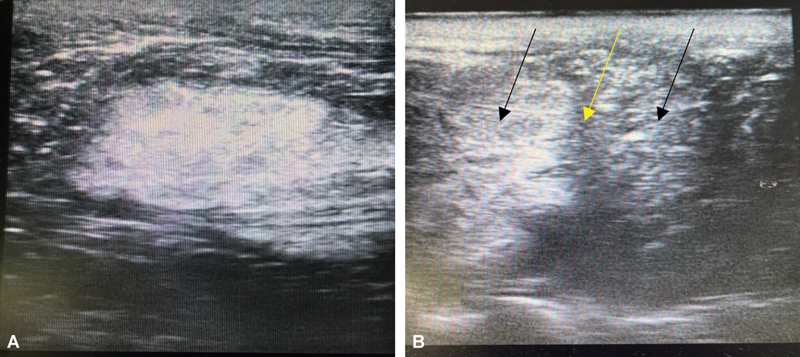

Lhermitte-Duclos disease (LDD) is a rare, autosomal dominant, dysplastic gangliocytoma of the cerebellum. It is a slow-growing benign tumor. The challenges in the surgical resection of these tumors lie in accurately delineating the tumor margin from the normal cerebellar parenchyma. Intraoperative ultrasound has the potential to overcome these limitations. A 30-year-old woman was diagnosed as having LDD showing a typical "tigroid" appearance on MRI. Intraoperative ultrasound was used to delineate the tumor margins and near-total resection was done via right suboccipital craniectomy. The diagnosis was confirmed on histopathological examination. Postoperatively there were no neurological deficits, and the patient is on regular follow-up for screening of Cowden's syndrome. We report this case to highlight the undervalued utility of intraoperative ultrasonography while dealing with patients with LDD. This modality serves as an effective tool to maximize the extent of resection without adding to postoperative morbidity.